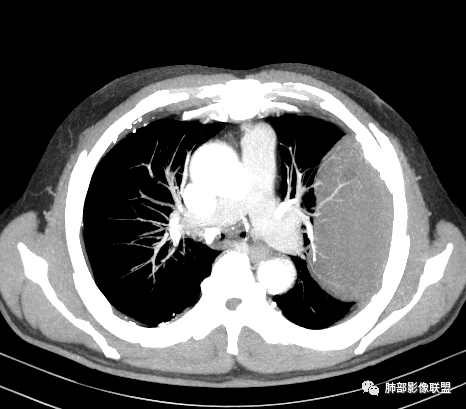

老年男性,糖尿病病史,消瘦、乏力三个月,影像表现左肺上叶胸膜下团块,有一定张力,内部疏松,可见支气管影及坏死区,增强病灶边缘环形强化,内部未见强化,考虑炎性肉芽肿病变,隐球?奴卡?放线菌?鉴别淋巴瘤。

增强没有强化,血管束正常,气管束有正常有扩张,内有空洞,考虑炎性病变,隐球?

我要修正一下观点了:仔细看了视频,肿块占位效应明显,对周围血管,支气管有推挤,增强后强化不明显,NSE增高,半年体重下降25公斤,虽然有内部支气管扩张,血管漂浮,边界清楚支持淋巴瘤,但强化太低,膨隆,占位推挤太明显(淋巴瘤一般没有这么明显的占位效应),胸膜关系有载桩,恶病质明显(乏力,半年体重下降了25公斤),NSE也明显增高,就不支持淋巴瘤了。还是考虑外朝内的恶性肿瘤,间质来源的肉瘤伴有神经内分泌分化或者大神泌。

不支持淋巴瘤的有四点:1、对周围血管支气管推挤明显。2、胸膜有栽桩,3、强化太弱(淋巴瘤一般还是中度以上甚至高度强化多见),4、NSE升高明显,体重下降太明显。

老年男性,糖尿病病史,消瘦、乏力三个月,肿瘤标志物高。左肺上叶胸膜下肿块,边界清晰,可见支气管影及坏死区,增强病灶边缘强化,内部未见明显强化,邻近胸膜有累及,考虑恶性,建议穿刺活检。

5)肿瘤强化方式:肺部恶性肿瘤强化程度与其血供丰富程度相关,血供丰富多强化明显,反之则较差。由于PSC 周边实性部分富血供及内部黏液变性、坏死,增强后肿块多数呈轻-中度边缘环形强化或不均匀小斑片状强化。国外学者对照病理发现肿瘤细胞或胶原组织增强扫描时强化,无强化的低密度区代表了黏液样变性区和出血坏死区。